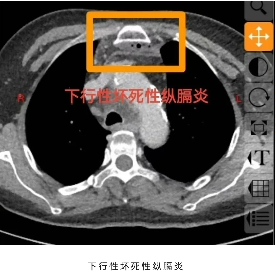

阳光讯(记者郑亚雷 通讯员 陈萌)60岁的庄女士未曾想到,一场看似寻常的牙痛,竟会迅速发展为危及生命的重症。庄女士糖尿病多年未经规范治疗,口腔卫生欠佳,口内牙齿时不时疼痛、松动、脱落,患者总认为牙疼是小毛病,吃点甲硝唑就好了,从未重视。5 天前,左下后牙疼痛后患者依旧未经重视,很快就出现咽部、颈部疼痛伴吞咽困难,在当地医院接受抗感染治疗,病情却未见好转,还出现难以忍受的胸部疼痛,叠加吞咽、呼吸困难等症状,被救护车紧急送往西安市红会医院耳鼻咽喉头颈整形修复科。经诊断,庄女士为 “颞下、咽旁、翼下颌、颌下间隙感染,颈部坏死性筋膜炎、下行性坏死性纵膈炎”,病情及其危重,需要头颈外科、胸外科、内分泌科等多学科联合救治,此类疾病非常凶险,死亡率较高,为患者办理住院后转入急诊重症监护室(EICU),一场与死神的赛跑就此拉开序幕。

在这场救治中,多学科协作的优势展现得淋漓尽致。EICU 凭借专业的重症监护能力,为患者搭建起稳固的生命支持防线,实时监测病情变化,为后续治疗争取宝贵时间;内分泌代谢科成为 “血糖管控尖兵”,针对庄女士血糖控制不佳的关键问题,精准调整降糖方案 ——血糖波动是感染扩散的重要推手,若血糖失控,不仅会加重感染,还会阻碍伤口愈合,内分泌团队的精准干预,从源头为感染控制筑牢屏障;胸部外科则在患者纵膈感染、脓胸治疗中发挥核心作用,参与联合手术,尤其是胸腔镜下脓胸切开引流术,为清除胸腔感染病灶提供了关键技术支持;神经内科密切关注患者神经功能状态,通过促醒等治疗保障神经功能稳定;营养膳食科结合患者感染重、消耗大的特点,定制科学营养方案,为机体修复提供能量支撑;而耳鼻咽喉头颈整形修复科作为牵头科室,始终把控治疗全局,精准判断手术时机与方案,三次手术层层递进 —— 从首次左侧咽旁间隙、颈部、前上纵隔清创+ VSD引流术,到联合胸部外科的二次多部位清创与胸腔镜引流,感染控制后第三次手术关闭切口,每一步都精准针对感染病灶,为清除感染、控制病情进展奠定基础。